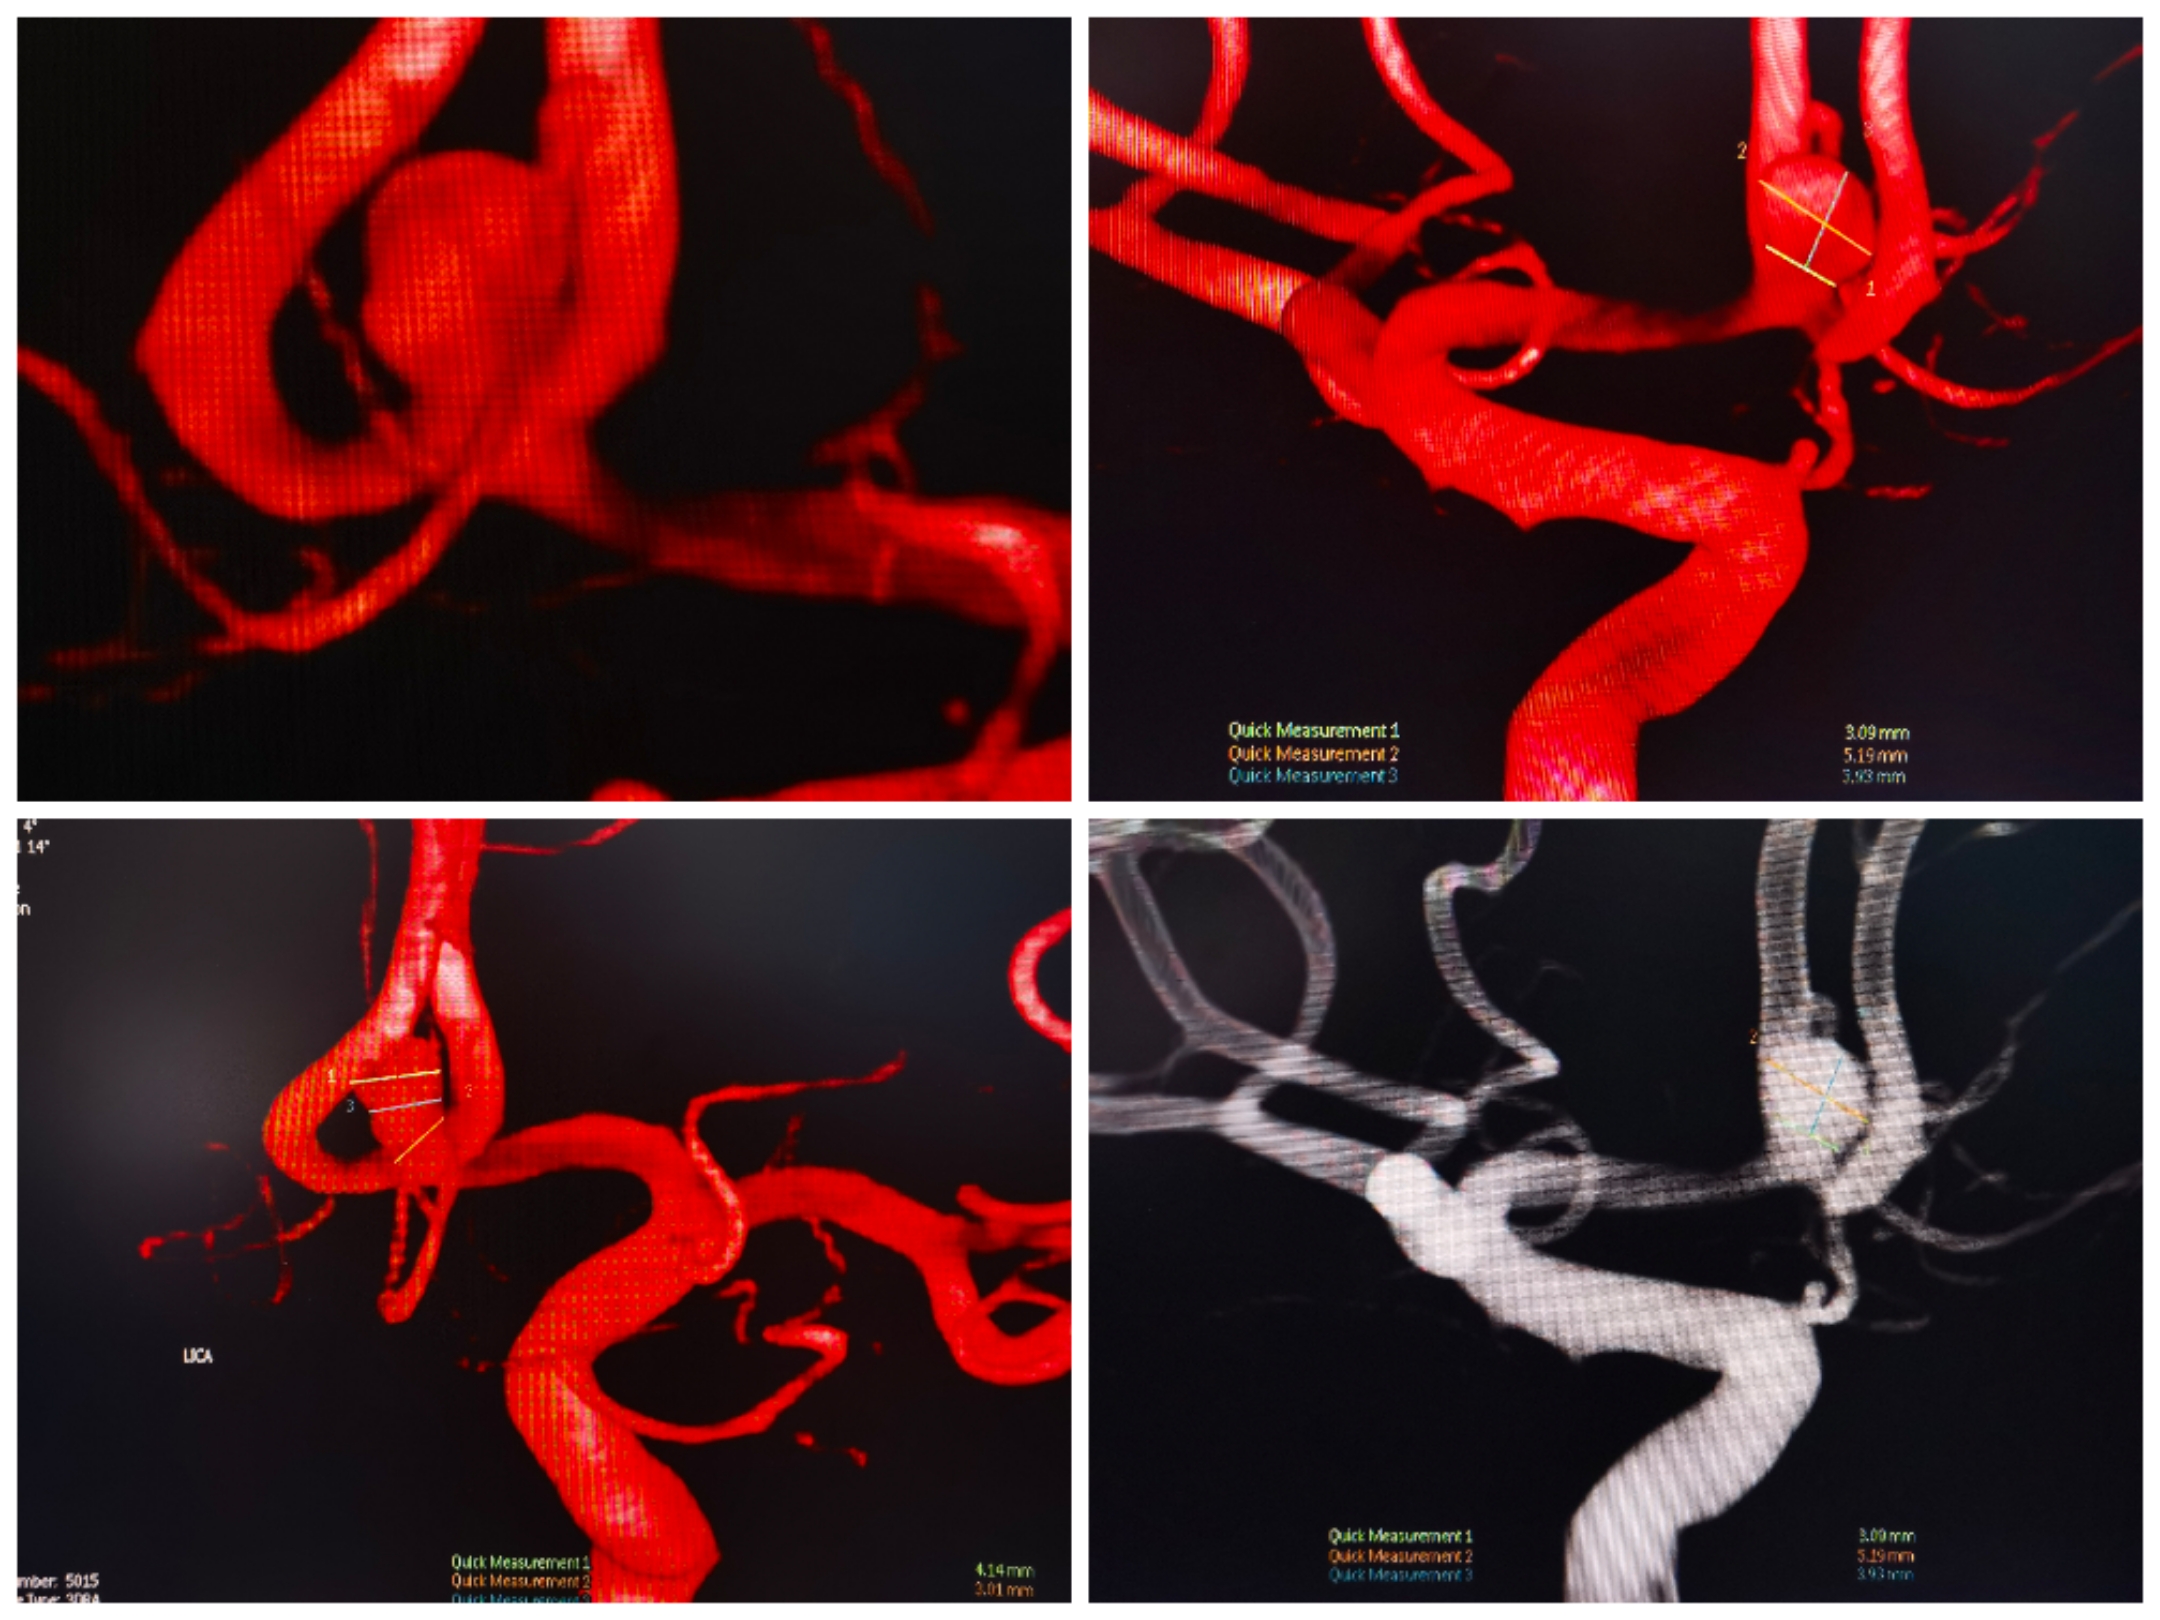

患者男性,体检发现未破裂动脉瘤入院,入院前已双抗药物准备5天,入院造影提示前交通动脉瘤。右侧A1缺如,左侧大脑前优势供血

3D重建提示宽颈前交通动脉瘤,瘤颈偏向同侧A2。手术计划:支架置入同侧A2,利用开环支架穹窿效应保护对侧A2,行弹簧圈栓塞。WEB也是个不错的选择,可惜手上没有材料。

微导管塑形情况。

支架导管、微管到位情况